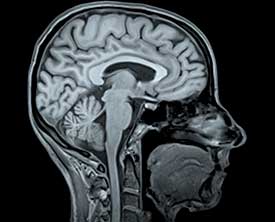

Способы диагностики

Ключевыми методами для проведения диагностического обследования являются:

- Магнитно-резонансная томография (МРТ).

Как диагностируется тромб в голове?

Диагностика тромба в голове обычно включает нейровизуализацию, такую как компьютерная томография (КТ) или магнитно-резонансная томография (МРТ), которые помогают выявить наличие тромба и оценить состояние мозга. Также могут быть проведены анализы крови для определения факторов риска.